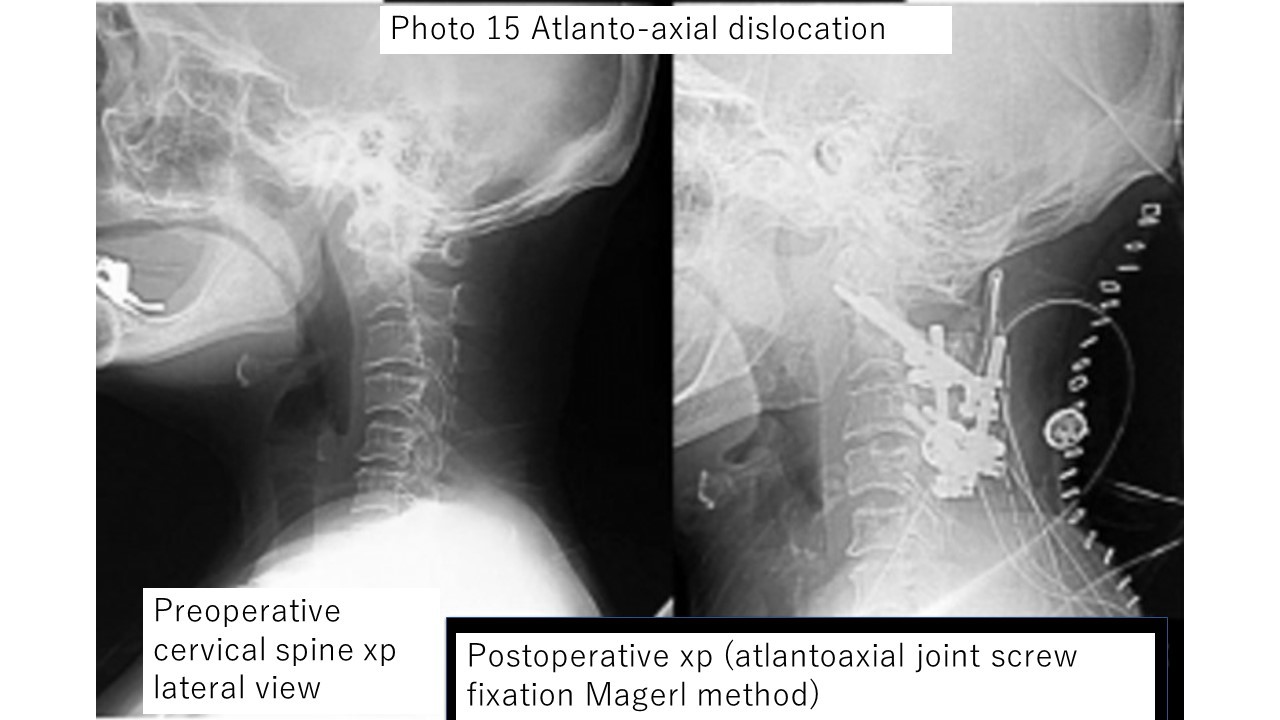

Photo 15: Atlantoaxial subluxation is a terrifying condition in which the first cervical vertebra (called the atlas) and the second cervical vertebra (called the axis) are misaligned, and in severe cases breathing may stop.

The image on the left is before surgery, and the image on the right is after surgery.

The atlas and axis are firmly fixed with large screws.

The patient was discharged from the hospital on foot with no new symptoms after surgery.